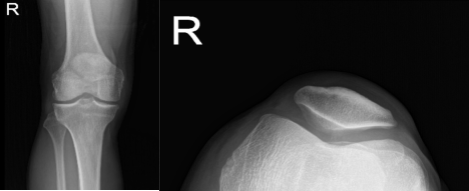

He was physically examined and an MRI was performed, which showed a complete tear of the quadriceps along with lateral meniscus tear, and partial tear of the ACL. The patient came to the emergency room due to intractable pain. We discussed treatment options and the patient opted for surgical management.

The patient underwent arthroscopic surgery. The procedures conducted were partial lateral meniscectomy, chondroplasty, ACL debridement and open repair of the quadriceps of the left knee. A left lateral entry portal was made and the scope was entered.

The scope was moved to the patellofemoral joint where trochlea grade 2 to grade 3 chondral damage was found. The chondral damage was debrided from the medial portal and followed by the lateral portal.

Copious lavage was performed. Arthroscopic pictures were taken and saved. The scope was removed. The knee was extended. The table was extended and a proper draping was performed. A midline vertical incision was put and centered over the superior pole of the patella.